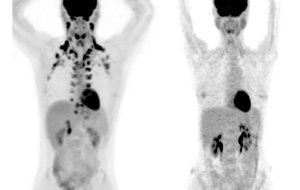

Study of 50,000 people finds brown fat may protect against numerous chronic diseases

Study of 50.000 people finds brown fat may protect against numerous chronic diseases Brown fat is that magical tissue that